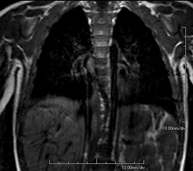

- RM del Mediastí

Prova diagnòstica no invasiva que consisteix en l'obtenció d'imatges d'alta definició anatòmica del mediastí mitjançant l'ús d'un camp electromagnètic i ones de ràdio (amb un emissor i un receptor). No utilitza radiació ionitzant. El mediastí és la part central de la caixa toràcica que inclou el tim, els grans vasos (aorta toràcica, vena cava inferior i superior, etc.), el cor, la tràquea i els bronquis principals, els ganglis limfàtics mediastínics i hilars, l'esòfag, etc. Està especialment indicada en lesions mediastíniques per diferenciar si són quístiques o sòlides, en el diagnòstic diferencial de les lesions del mediastí anterior, etc. De vegades s'ha d'emprar contrast paramagnètic (Gadolini) per completar l'estudi. - RM Tòrax

Prova diagnòstica no invasiva que consisteix en l'obtenció d'imatges d'alta definició anatòmica del tòrax mitjançant l'ús d'un camp electromagnètic i ones de ràdio (amb un emissor i un receptor). No utilitza radiació ionitzant. Està indicada en aquelles lesions pulmonars en les quals s'ha de descartar si hi ha infiltració del mediastí o de la paret toràcica, per diferenciar si una lesió toràcica és sòlida o quística, etc. En alguns casos caldrà emprar contrast paramagnètic (Gadolini) per completar l'estudi. - RM de Paret Toràcica